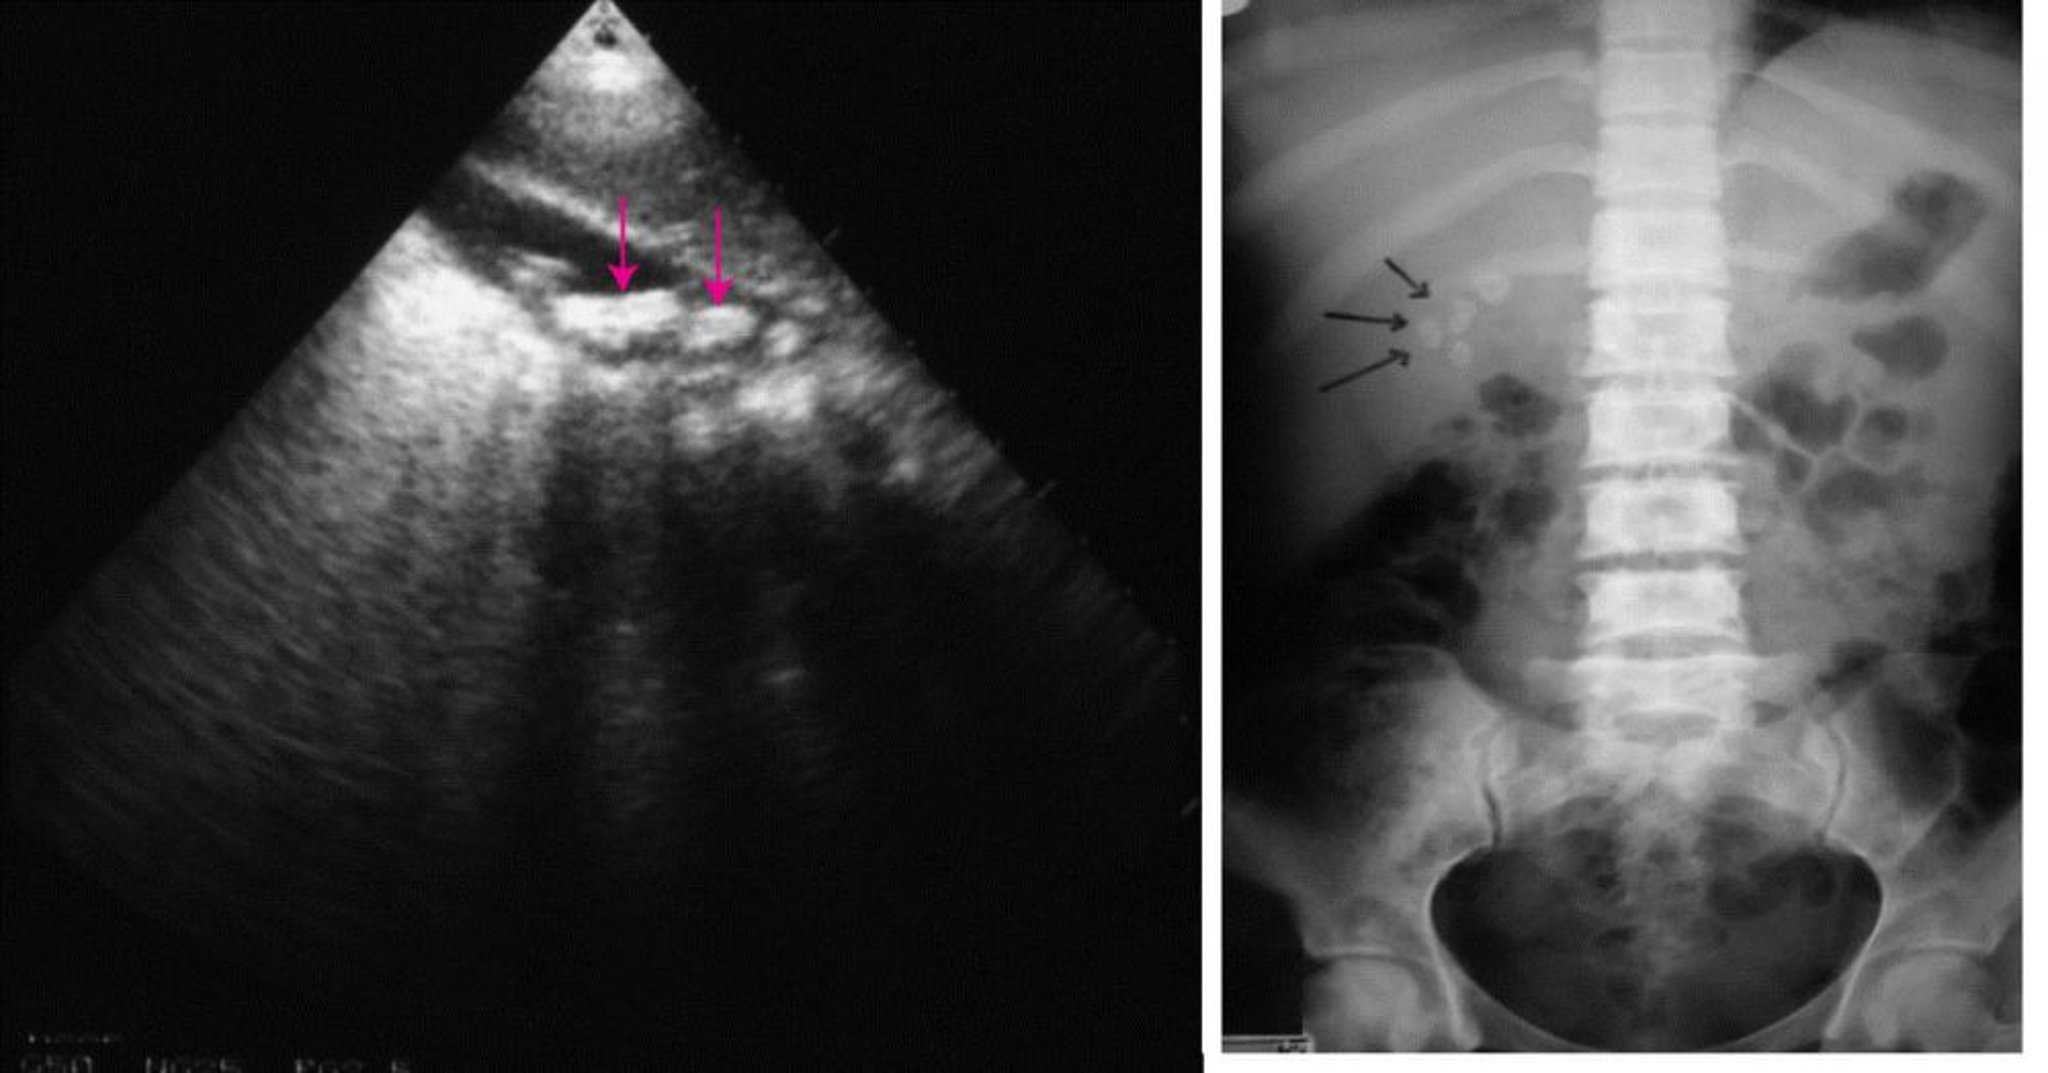

Imágenes abdominales (cálculos biliares)

A la izquierda, una ecografía abdominal que muestra múltiples cálculos biliares (flechas). A la derecha, una radiografía simple de abdomen que muestra cálculos biliares radiopacos (flechas).